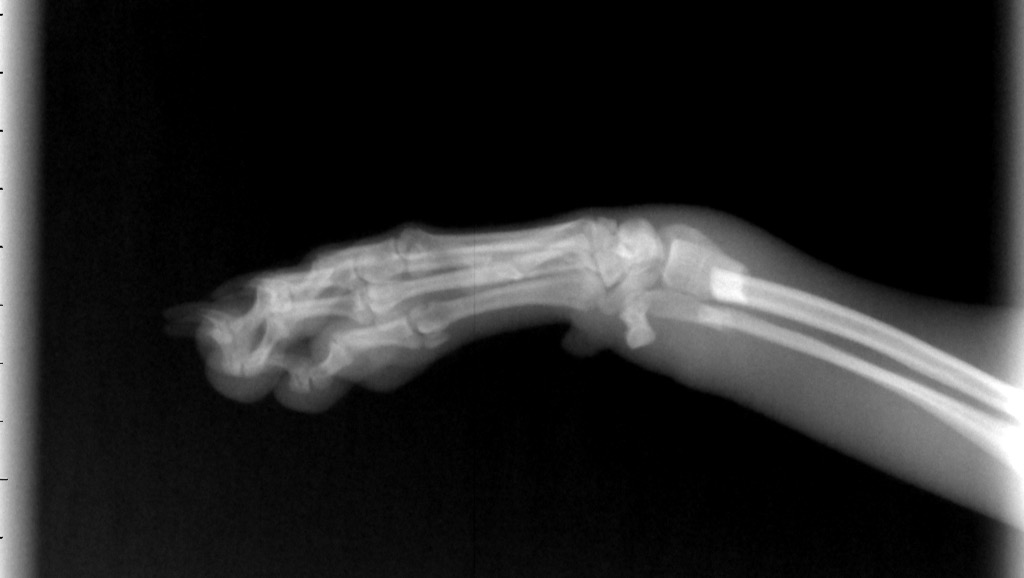

The vets called us and said they need to sedate her to do x-rays. She has two broken bones on her leg. Will attach photos of the X-rays.

The vets said she needs surgery, they sent the X-rays to a surgeon to give us a quote.

Estimate is $3,160.73 for Daisy's surgery where they need to put a plate in.